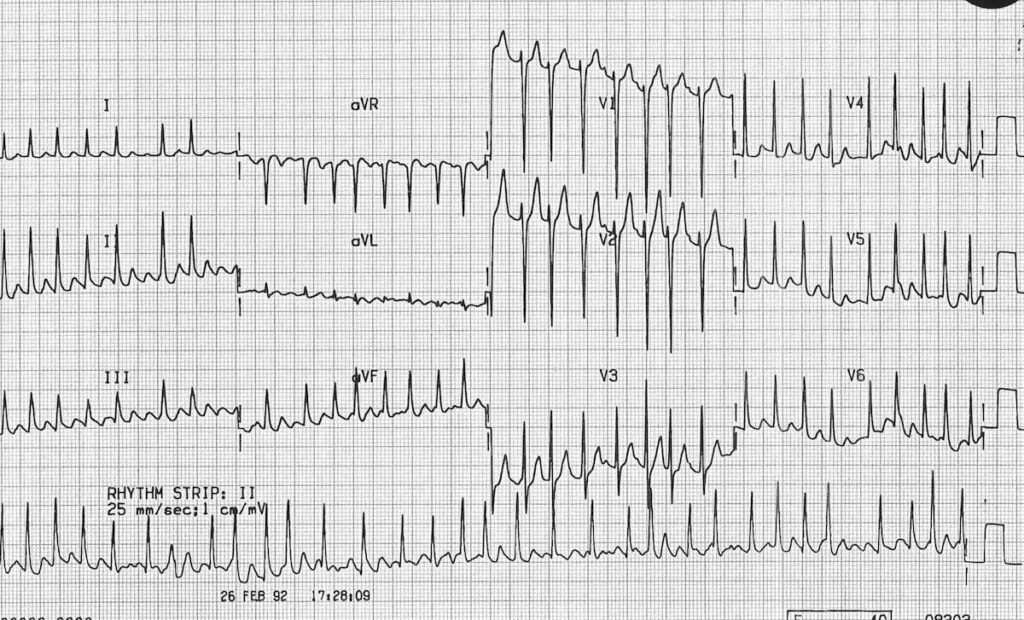

For at forstå betydningen af en inverteret T-tak, er det vigtigt først at vide, hvad T-takken repræsenterer. Et EKG registrerer hjertets elektriske aktivitet. Hvert hjerteslag består af en cyklus af elektriske impulser, der vises som forskellige bølger på EKG-strimlen. T-takken er den bølge, der følger efter det store QRS-kompleks, og den repræsenterer den fase, hvor hjertekamrene (ventriklerne) 'nulstiller' sig elektrisk efter at have trukket sig sammen. Denne fase kaldes repolarisering.

- Den er typisk opretstående (positiv) i de fleste afledninger, undtagen aVR og nogle gange V1.

- Amplituden er normalt under 5 mm i ekstremitetsafledningerne og under 10 mm i prækordialafledningerne.

- Formen er let asymmetrisk med en langsommere opadgående hældning og en hurtigere nedadgående hældning.